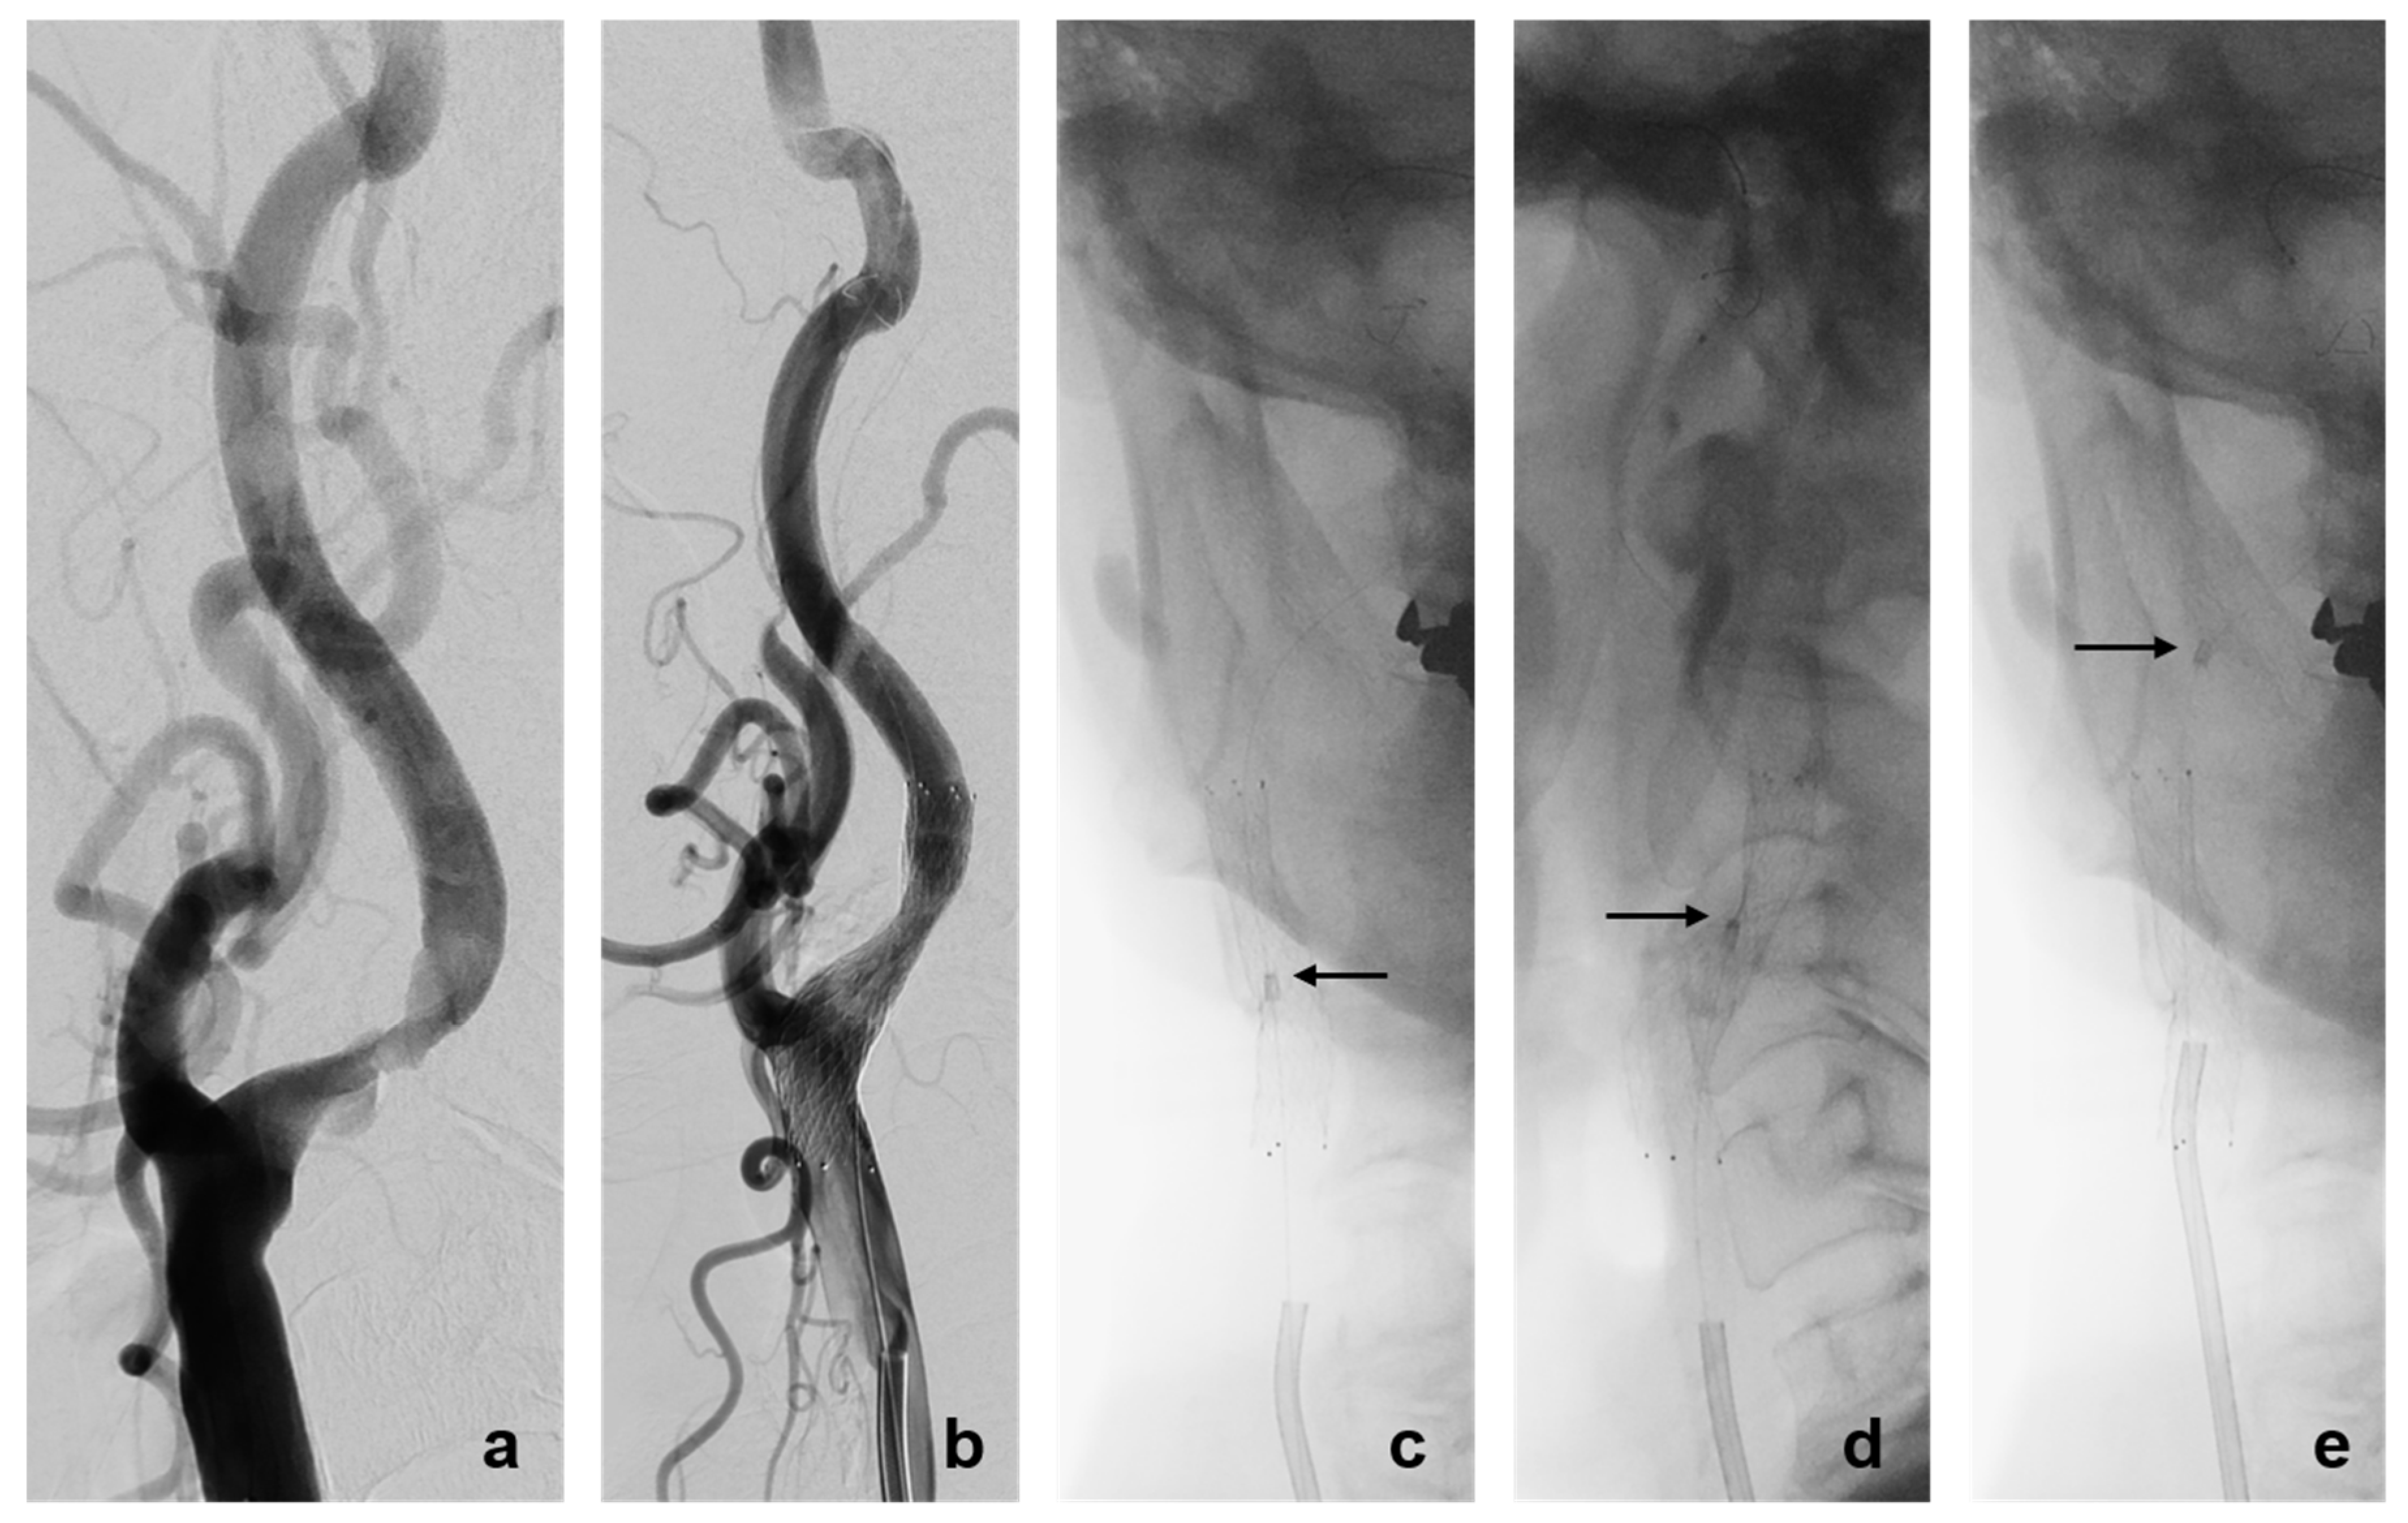

3.2. Rescue Techniques for Adverse Events Related to EPD